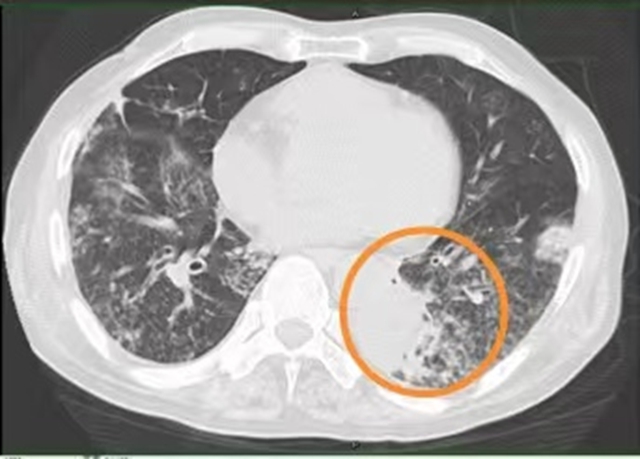

入院后,医生给王大爷用了抗感染、止咳化痰、营养支持等治疗,可3天过去,王大爷喘息、气促、咳嗽、咯黄痰仍没缓解,胸壁包块也没缩小,包块局部触摸还有波动感。复查胸部CT提示:双肺多发结节影、磨玻璃影、斑片影,部分见肺实变影,部分支气管牵拉扩张,左肺下叶部分支气管闭塞。

“终于找到凶手了!”敖素华教授立刻调整治疗方案,用上了针对诺卡菌的抗生素。用药1周后,王大爷的咳嗽明显减轻,黄痰减少,胸壁的包块慢慢缩小,2周后复查CT提示双肺炎症减少。